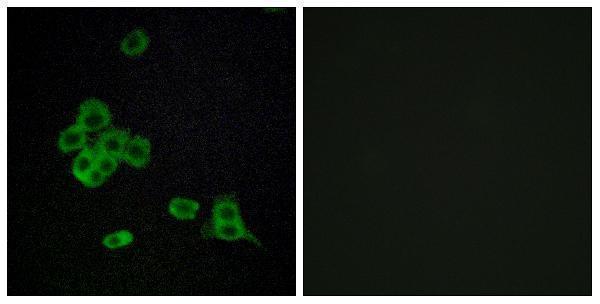

Facts about Cadherin-like protein 26.

| Gene Name: | CDH26 |

Cell membrane; Single-pass type I membrane protein.